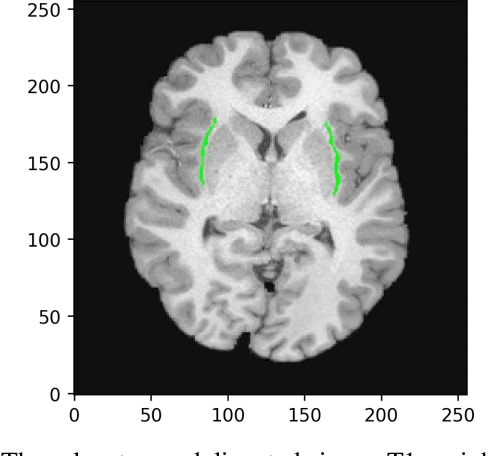

In recent years, Deep Learning (DL) has shown promising results in conducting AI tasks such as computer vision and image segmentation. Specifically, Convolutional Neural Network (CNN) models in DL have been applied to prevention,detection, and diagnosis in predictive medicine. Image segmentation plays a significant role in disease detection and prevention.However, there are enormous challenges in performing DL-based automatic segmentation due to the nature of medical images such as heterogeneous modalities and formats, insufficient labeled training data, and the high-class imbalance in the labeled data. Furthermore, automating segmentation of medical images,like magnetic resonance images (MRI), becomes a challenging task. The need for automated segmentation or annotation is what motivates our work. In this paper, we propose a fully automated approach that aims to segment the human claustrum for analytical purposes. We applied a U-Net CNN model to segment the claustrum (Cl) from a MRI dataset. With this approach, we have achieved an average Dice per case score of 0.72 for Cl segmentation, with K=5 for cross-validation. The expert in the medical domain also evaluates these results.